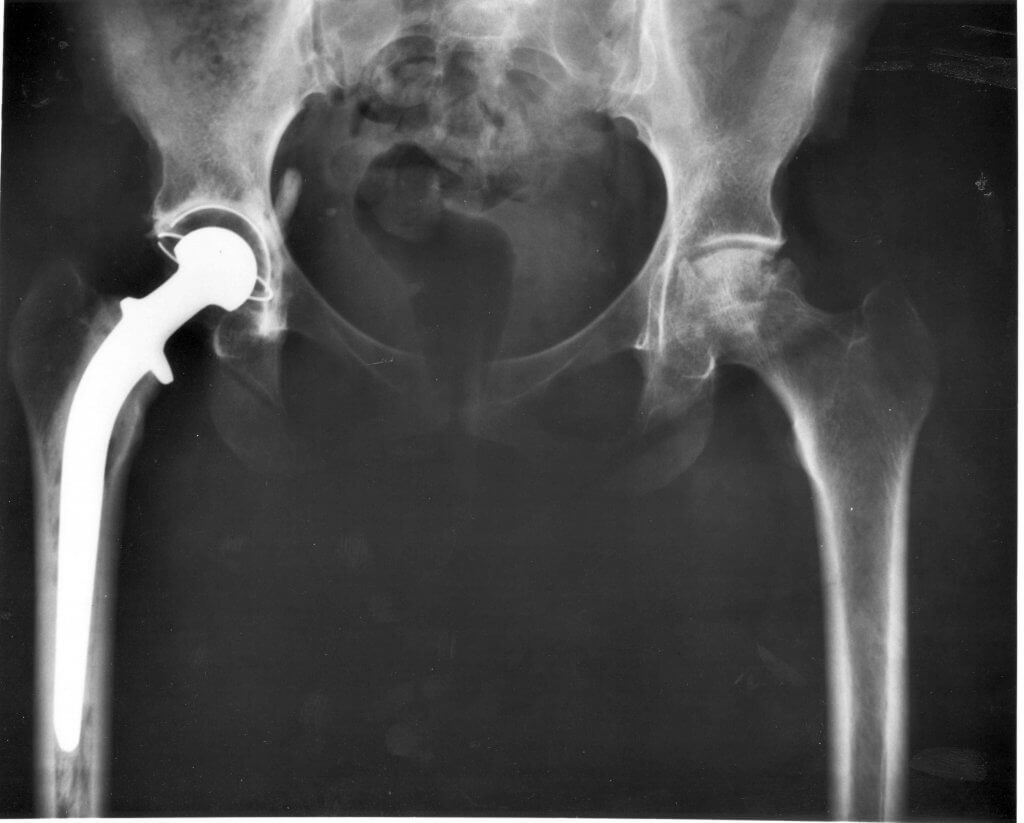

Dein Tierarzt wird die Hüftgelenke untersuchen und entsprechende Röntgenaufnahmen des Beckenbereichs machen, um das Problem zu identifizieren. Nach der Diagnose gibt es verschiedene Behandlungsmethoden, um die Symptome zu lindern und das Fortschreiten zu verhindern.

Bei weiter fortgeschrittenen Fällen kann man auch eine Operation durchführen, die sogar einen vollständigen Ersatz der Hüfte umfassen kann.